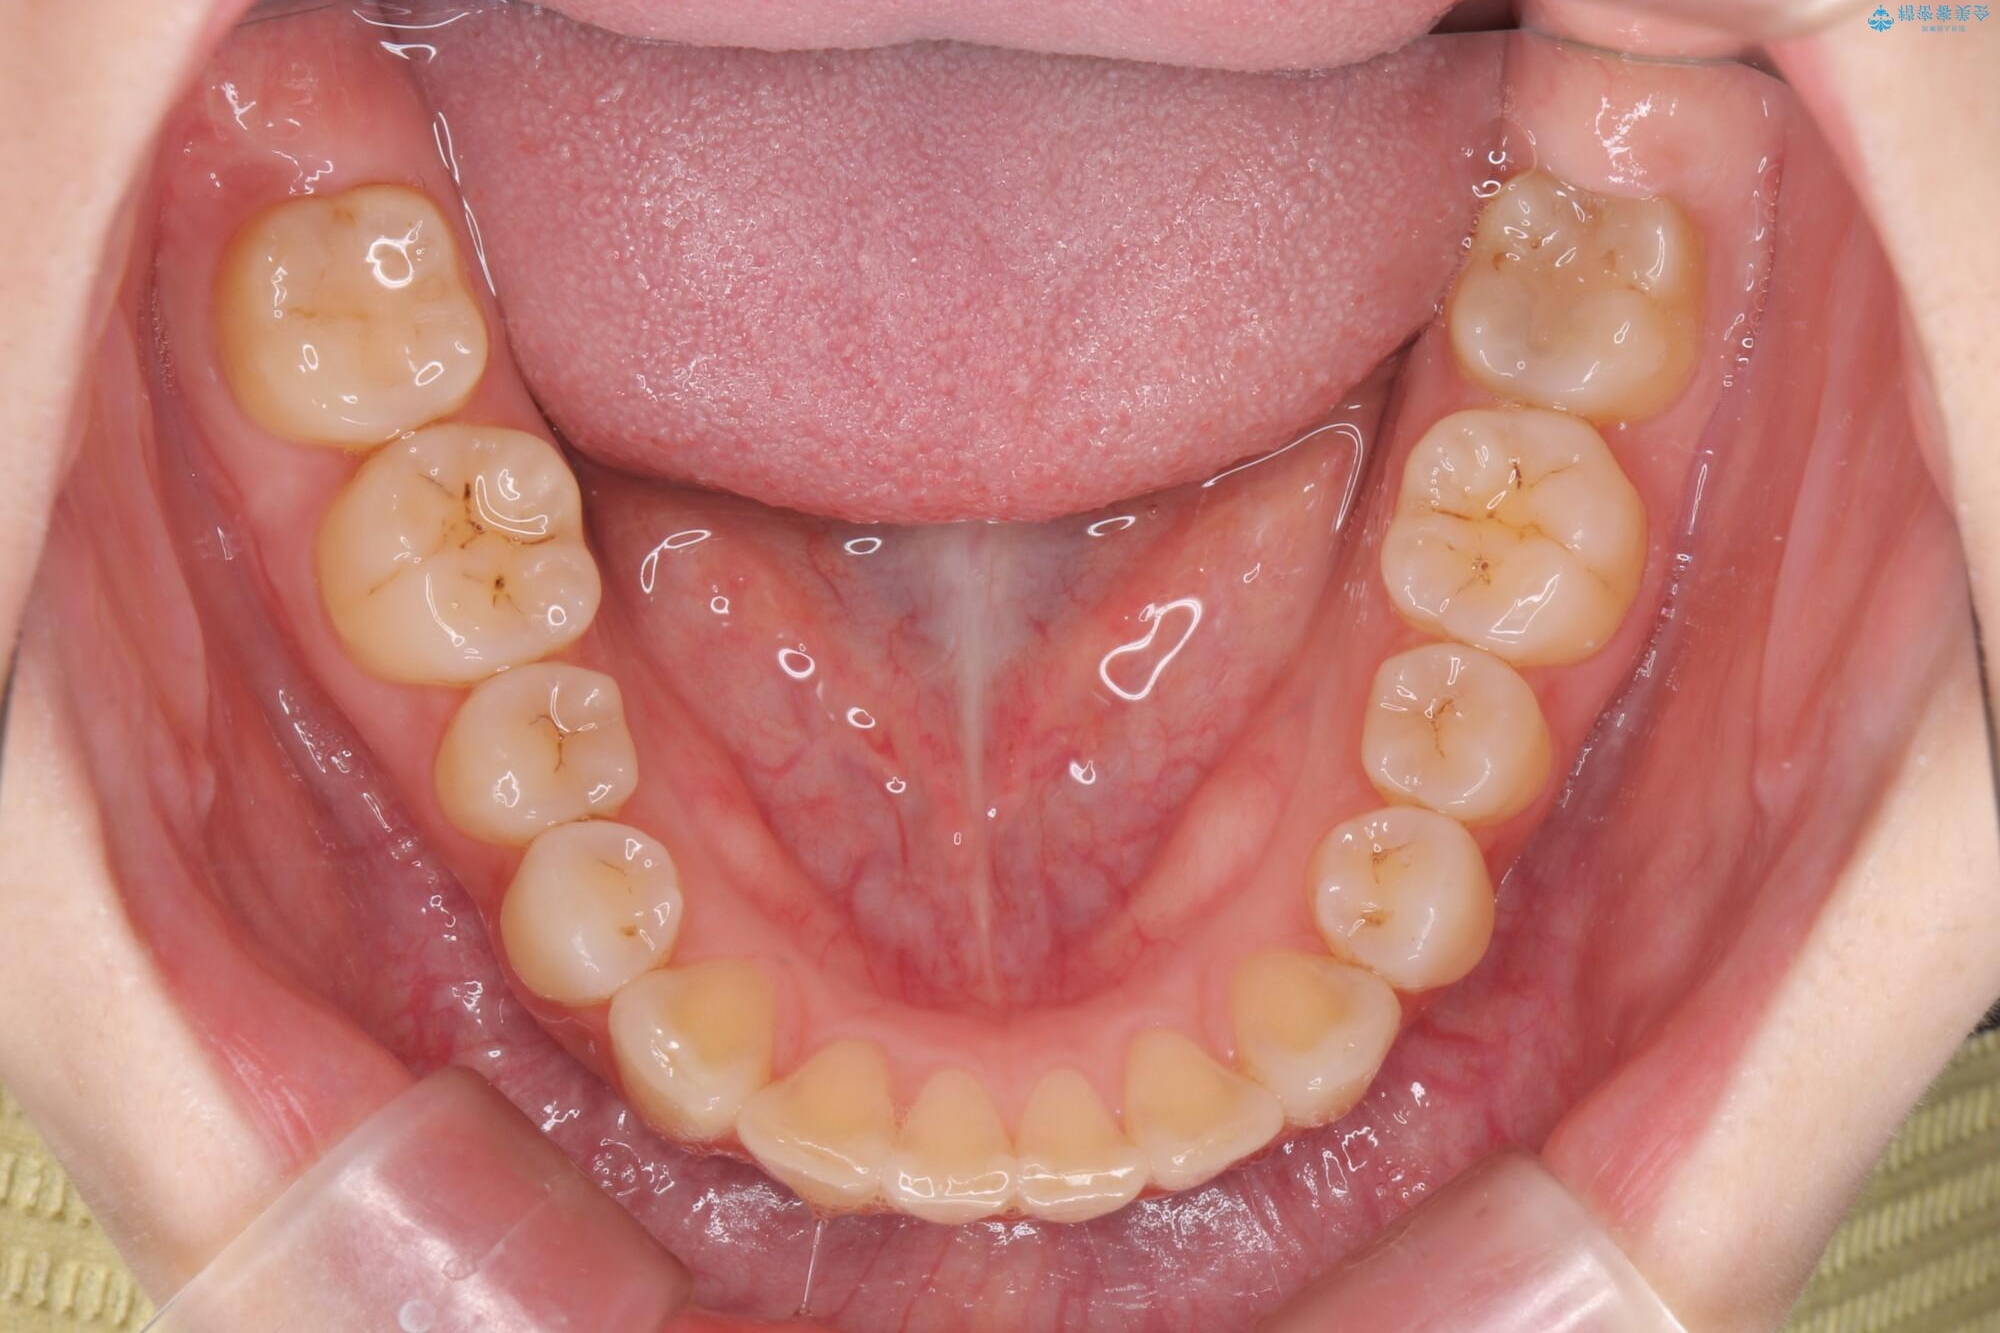

治療前

傾いた前歯、インビザラインで改善 治療前画像 傾いた前歯、インビザラインで改善 治療前画像 傾いた前歯、インビザラインで改善 治療前画像 傾いた前歯、インビザラインで改善 治療前画像